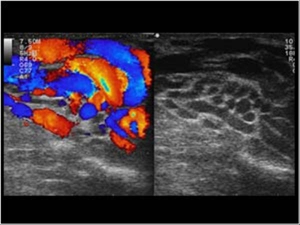

ΑΠΕΙΚΟΝΙΣΤΙΚΑ ΕΥΡΗΜΑΤΑ

Ο απεικονιστικός έλεγχος ενδείκνυται σε περιπτώσεις έντονου πόνου και σε περιπτώσεις ανδρικής στείρωσης λόγω,μειωμένου αριθμού ή κινητικότητας των σπερματοζωαρίων,προκειμένου να αποκλεισθεί μία υποκλινική κιρσοκήλη.

Στο έγχρωμο DOPPLER υπερηχογράφημα(υπερηχητική φλεβογραφία οσχέου-έγχρωμο Triplex),το οποίο αποτελεί τη μέθοδο εκλογής και γίνεται αποκλειστικά απο Ιατρό Ακτινοδιαγνώστη,απεικονίζεται μία συλλογή από διατεταμένες ελικοειδείς φλέβες.Η κιρσοκήλη είναι ιδιαίτερα εμφανής σε όρθια θέση.